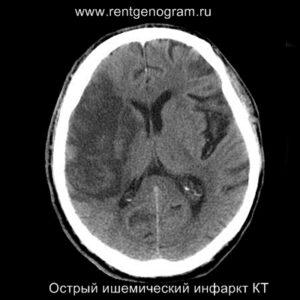

Ранние признаки ишемического инфаркта на КТ:

- уменьшение дифференциации серого и белого вещества;

- фокальная гипоплотность (включая островки, подкорковые ядра и кору);

- утолщение коры и сужение борозд;

- сглаживание контуров извилин и борозд;

- повышенная плотность в артерии (может быть выявлен гиперденсный тромб, обычно в СМА или ВСА);

- незначительная асимметрия мозговых структур в базальных ядрах;

- через 4-5 часов могут появиться признаки уменьшения плотности поврежденных структур мозга.

В течение острого этапа на МРТ и КТ выявляются все морфологические признаки ишемического инсульта. Область острого ишемического инфаркта визуализируется как зона ↑Т2, ↑Flair, ↑DWI и ↓Т1 ↓ADC. Можно обнаружить тромб в артерии. На КТ в остром этапе также чётко дифференцируется поражённая область, представляющая собой участок с потерей дифференциации мозговых структур и снижением их плотности. Контрастирование в остром периоде не показывает патологических участков с накоплением контраста.